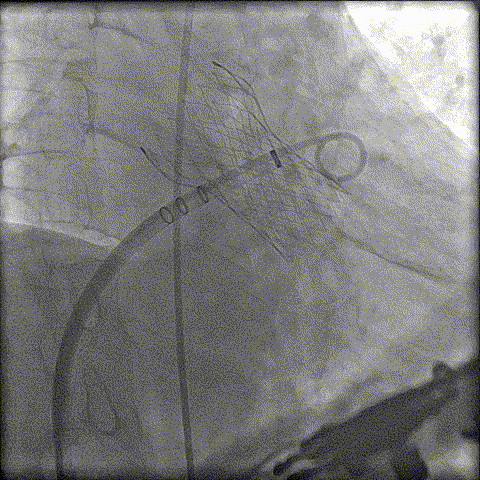

术前CT分析判断该心耳为反鸡翅型左心耳,选择偏下略偏前的位置进行房间隔穿刺。在工作体位造影后,可见左心耳内梳状肌发达,反鸡翅叶显影清晰,鞘管轴向佳。经DSA测量左心耳开口18mm深度17mm,结合TEE测量数据,综合考虑选用WATCHMAN24mm封堵器进行封堵。在展开封堵器时利用在体内借深度技巧,保证封堵器封堵位置合理。封堵器展开后经造影检查封堵器封堵效果理想,牵拉试验稳定。超声评估封堵器各角度无残余分流,位置理想,满足PASS原则,随即释放封堵器,一站式手术顺利结束。

左心耳造影

封堵器缓慢展开

即刻造影

释放封堵器